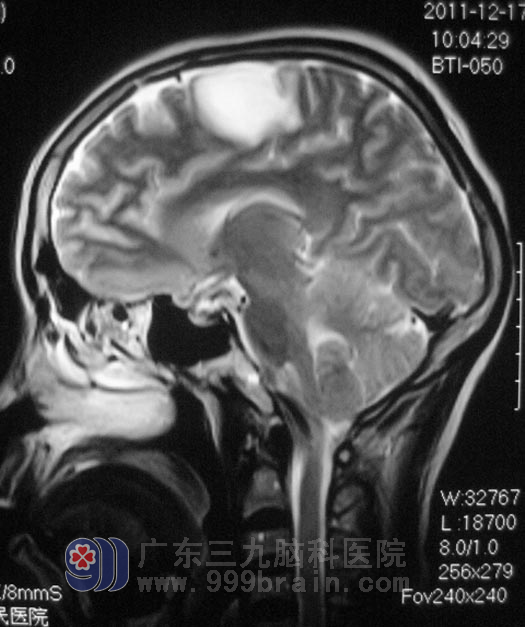

2011年12月16日,正聊着天的阿花突然出现四肢不自主抽搐摔倒在地上,持续约10分钟后自行缓解,家人将她送往当地医院,头颅CT检查结果提示:右侧额顶叶低密度影,MR检查示“右侧额顶叶异常信号影,直径约3cm,考虑胶质瘤或脑梗塞可能”。医生告知她的家人:手术可能会导致阿花瘫痪。

在广东三九脑科医院综合神经外科,鲁明主任初步考虑为胶质瘤。12月26日,鲁明主任主刀,为阿花行右侧额叶占位切除术,术中使用导航仪定位,见肿瘤位于右侧中央前回。术中唤醒麻醉结合电生理皮层电极检测及导航,手术全程让阿花在说话和肢体运动中进行。术后没有出现患者家属所担心的偏瘫情况,十天后,阿花四肢功能正常,办理出院。术后病理结果为:(右额叶)星形细胞瘤,WHO II 级。